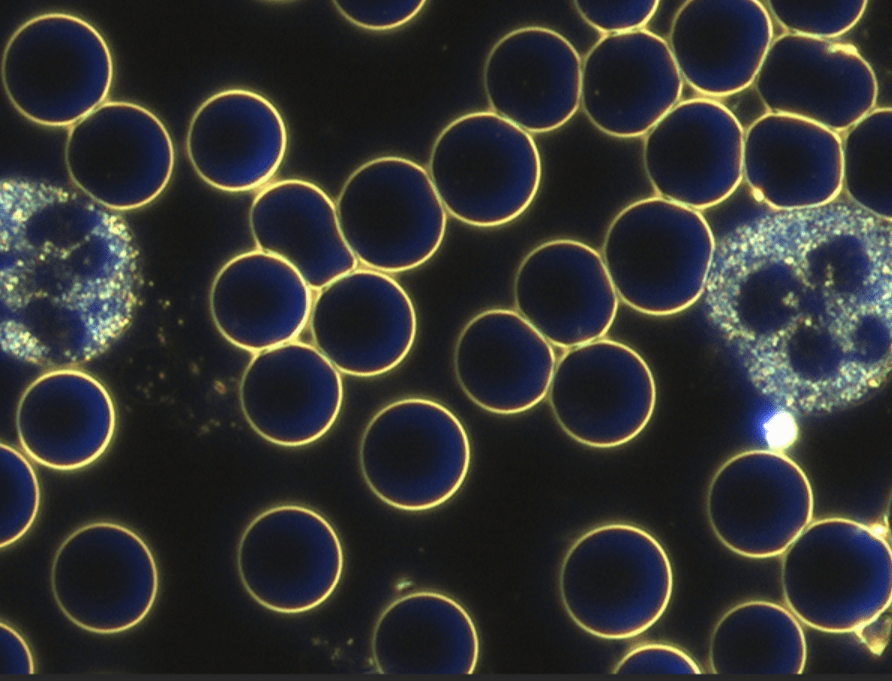

Manch Einer fragt sich warum werde ich krank und der Andere nicht. Mikroorganismen können sich unter bestimmten Verhältnissen einfach besser entwickeln. Ein gestörtes Körpermilieu ist der beste Nährboden für Erkrankungen. Genau hier setzt diese Untersuchungs- und Behandlungsmethode nach Prof. Dr. Enderlein an. Bei diesem Diagnoseverfahren wird mit Hilfe des Dunkelfeld-Mikroskops ein Tropfen Blut untersucht. Aufgrund der speziellen physikalischen Vorraussetzungen des Dunkelfeld-Mikroskops können Phänomene im Blut erkannt werden und so Rückschlüsse auf Veränderungen im Körpermilieu gezogen werden. Es wird die Anzahl, Form und Beweglichkeit der Weißen und roten Blutkörperchen untersucht, die Lage der Blutblättchen beurteilt und Erscheinungsformen im Plasma bestimmt.

Beispiele: